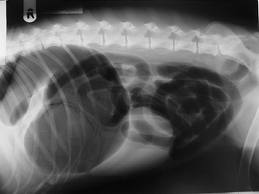

Source : Clinique Château

Une torsion d'estomac, aussi appelé "syndrome de dilatation-torsion d'estomac" est un phénomène extrêmement grave chez le chien qui implique un gonflement gastrique qui peut découler sur une rotation de l'estomac dans le ventre.Ce gonflement peut entraîner la rupture du ligament qui soutient l'estomac et la rate, et la circulation sanguine est perturbée. Ce phénomène est extrêmement douloureux pour l'animal.